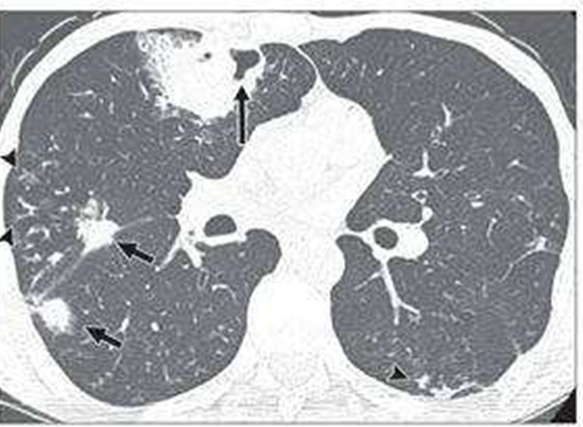

不同免疫抑制类型患者所特有的SCAP病原体,例如,粒缺患者首先考虑铜绿假单胞菌和曲霉感染的可能,艾滋病患者考虑肺孢子菌和结核分枝杆菌感染风险,T细胞耗竭(抗胸腺细胞球蛋白、阿伦单抗)患者考虑肺孢子菌、隐球菌以及单纯疱疹病毒感染,低丙种球蛋白血症患者考虑呼吸道合胞病毒感染,使用神经磷酸酶抑制剂(环孢素、他克莫司)患者要考虑诺卡菌或曲霉感染,使用雷帕霉素抑制剂的患者需考虑隐球菌或曲霉感染风险,使用糖皮质激素的患者首先考虑铜绿假单胞菌及肺孢子菌感染风险。

(5)免疫抑制患者的经验性抗诺卡菌指征,①宿主特征:实体器官移植术后(肺、心脏、肝脏),造血干细胞移植术后,未接受TMP-SMX预防治疗。②临床特征:肺炎合并肺脓肿或脑脓肿。③治疗推荐:TMP-SMX 15~20 mg/(kg·d)的甲氧苄啶。